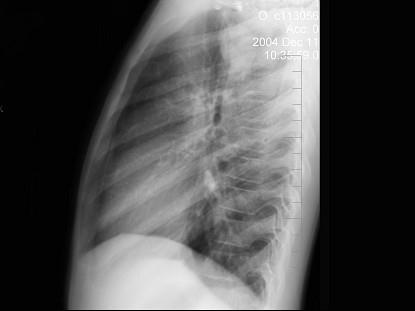

问题 患者男性,9岁,常年咳嗽,无其他自觉症状,X线检查如图所示,最可能的诊断是 ( )

选项 A、纵隔肿瘤 B、原发性肺癌 C、炎性假瘤 D、结核球

答案 C